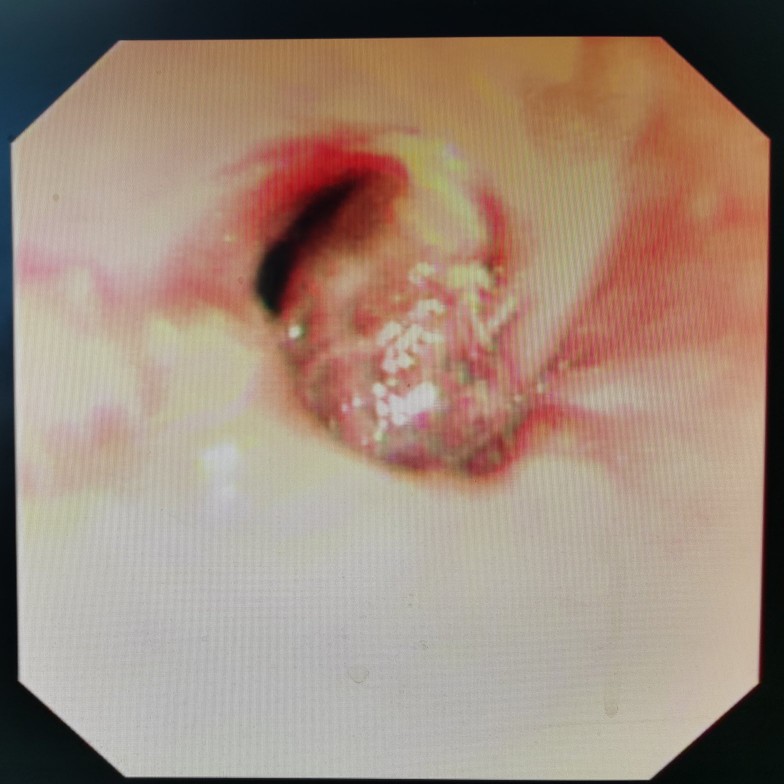

胃镜下看到的贲门肿瘤

从食管向胃方向看到的贲门肿瘤

贲门肿瘤已经快完全堵塞食管了